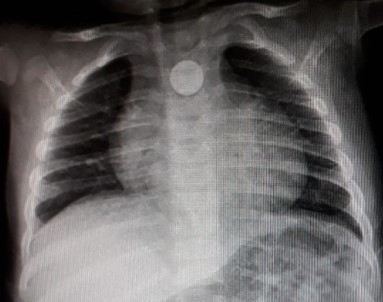

Bozuk para röntgen filminde ortaya çıktı

Yoğun bakıma alınan minik bebeğe önce film çekildi. 9 aylık Mustafa’nın boğazına takılan madeni para filmde ortaya çıkınca doktorlar tarafından operasyon yapıldı. Boğazındaki 1 lira çıkarılan minik bebek daha sonra rahat nefes almaya başladı.